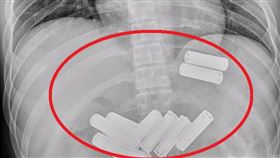

23歲男吞11顆電池!耗費1小時胃鏡取出

一位23歲的李先生因吞入11顆3號電池,半夜被緊急送...